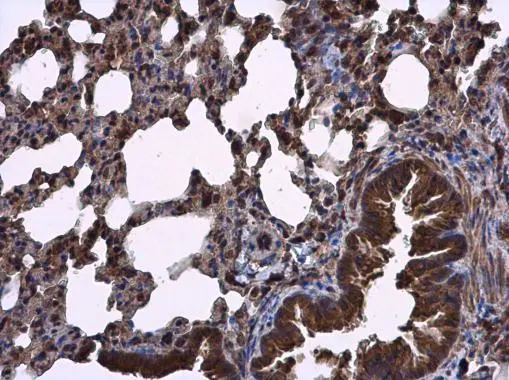

![RIPX antibody [N1C1] detects RIPX protein at cytoplasm in mouse lung by immunohistochemical analysis. Sample: Paraffin-embedded mouse lung. RIPX antibody [N1C1] (GTX118968) diluted at 1:500.

Antigen Retrieval: Citrate buffer, pH 6.0, 15 min](https://www.genetex.com/upload/website/prouct_img/normal/GTX118968/GTX118968_40408_20150724_IHC-P_M_w_23060519_425.webp)